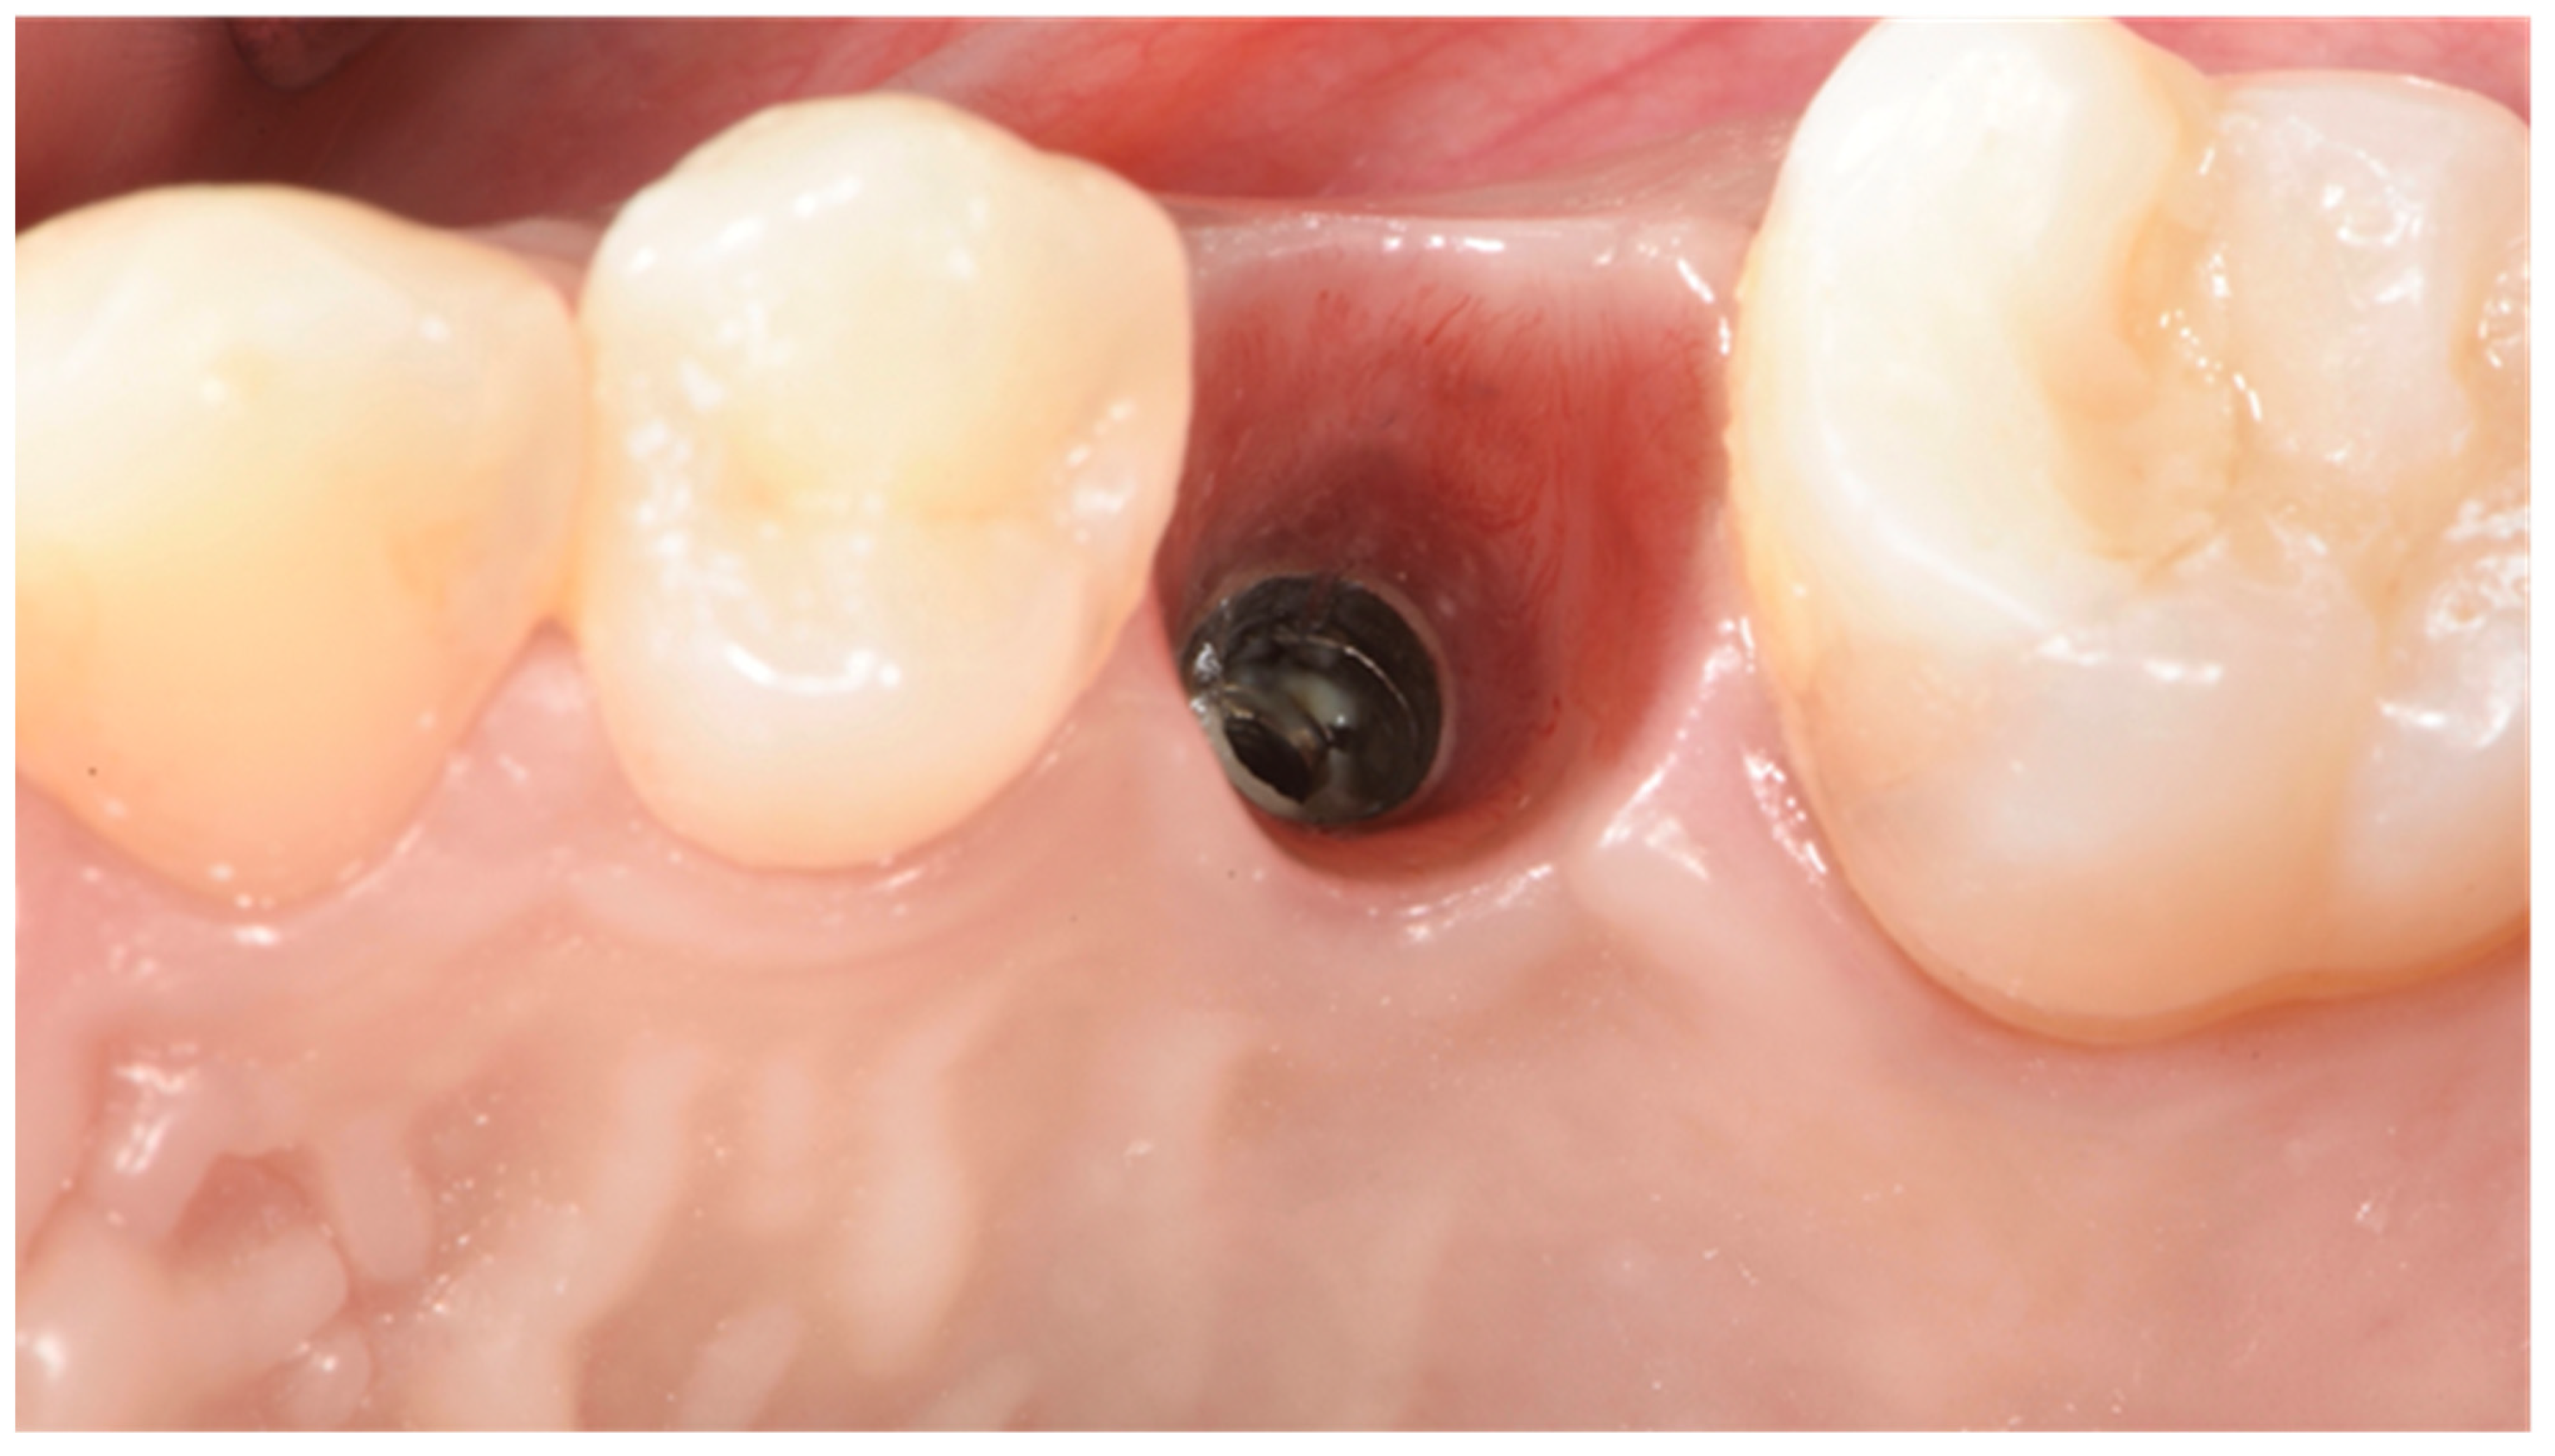

- Velásquez-Plata, D.; Lutonsky, J.; Oshida, Y.; Jones, R. A close-up look at an implant fracture: A case report. Int. J. Periodontics Restor. Dent. 2002, 22, 483–491. [Google Scholar]